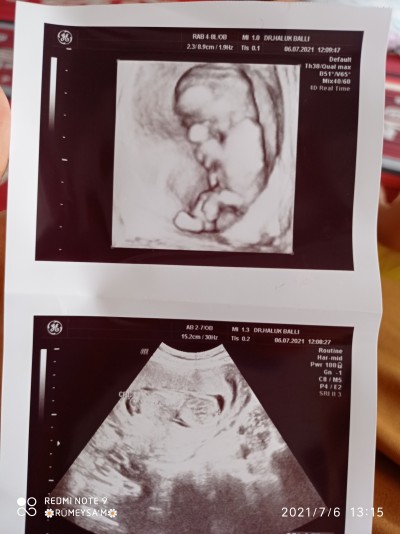

Bugün doktora gittim cinsiyetini öğrenemedik belliydi kordon TM cinsiyetinin olduğu kısımdaydı sizden cinsiyet tahmini alalım

Gebelik haftası 13+3